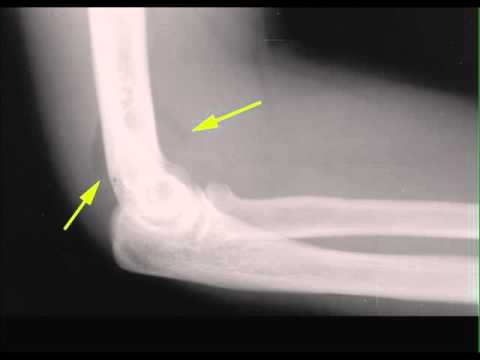

Positive Posterior Fat Pad. A lateral radiograph of the elbow shows a crescentric lucency projecting posterior to the distal humerus (white arrow) representing fat which has been displaced by an elbow joint effusion. Such effusions are frequently secondary to trauma and a subtle fracture of the neck of the radius is present (red arrow).

On annotated image lateral view: Positive posterior fat pad sign as indicated by yellow line in the olecranon fossa. This is not seen on normal elbow radiographs. The positive sail sign is highlighted in red, the latter represents superior displacement of the anterior fat pad.